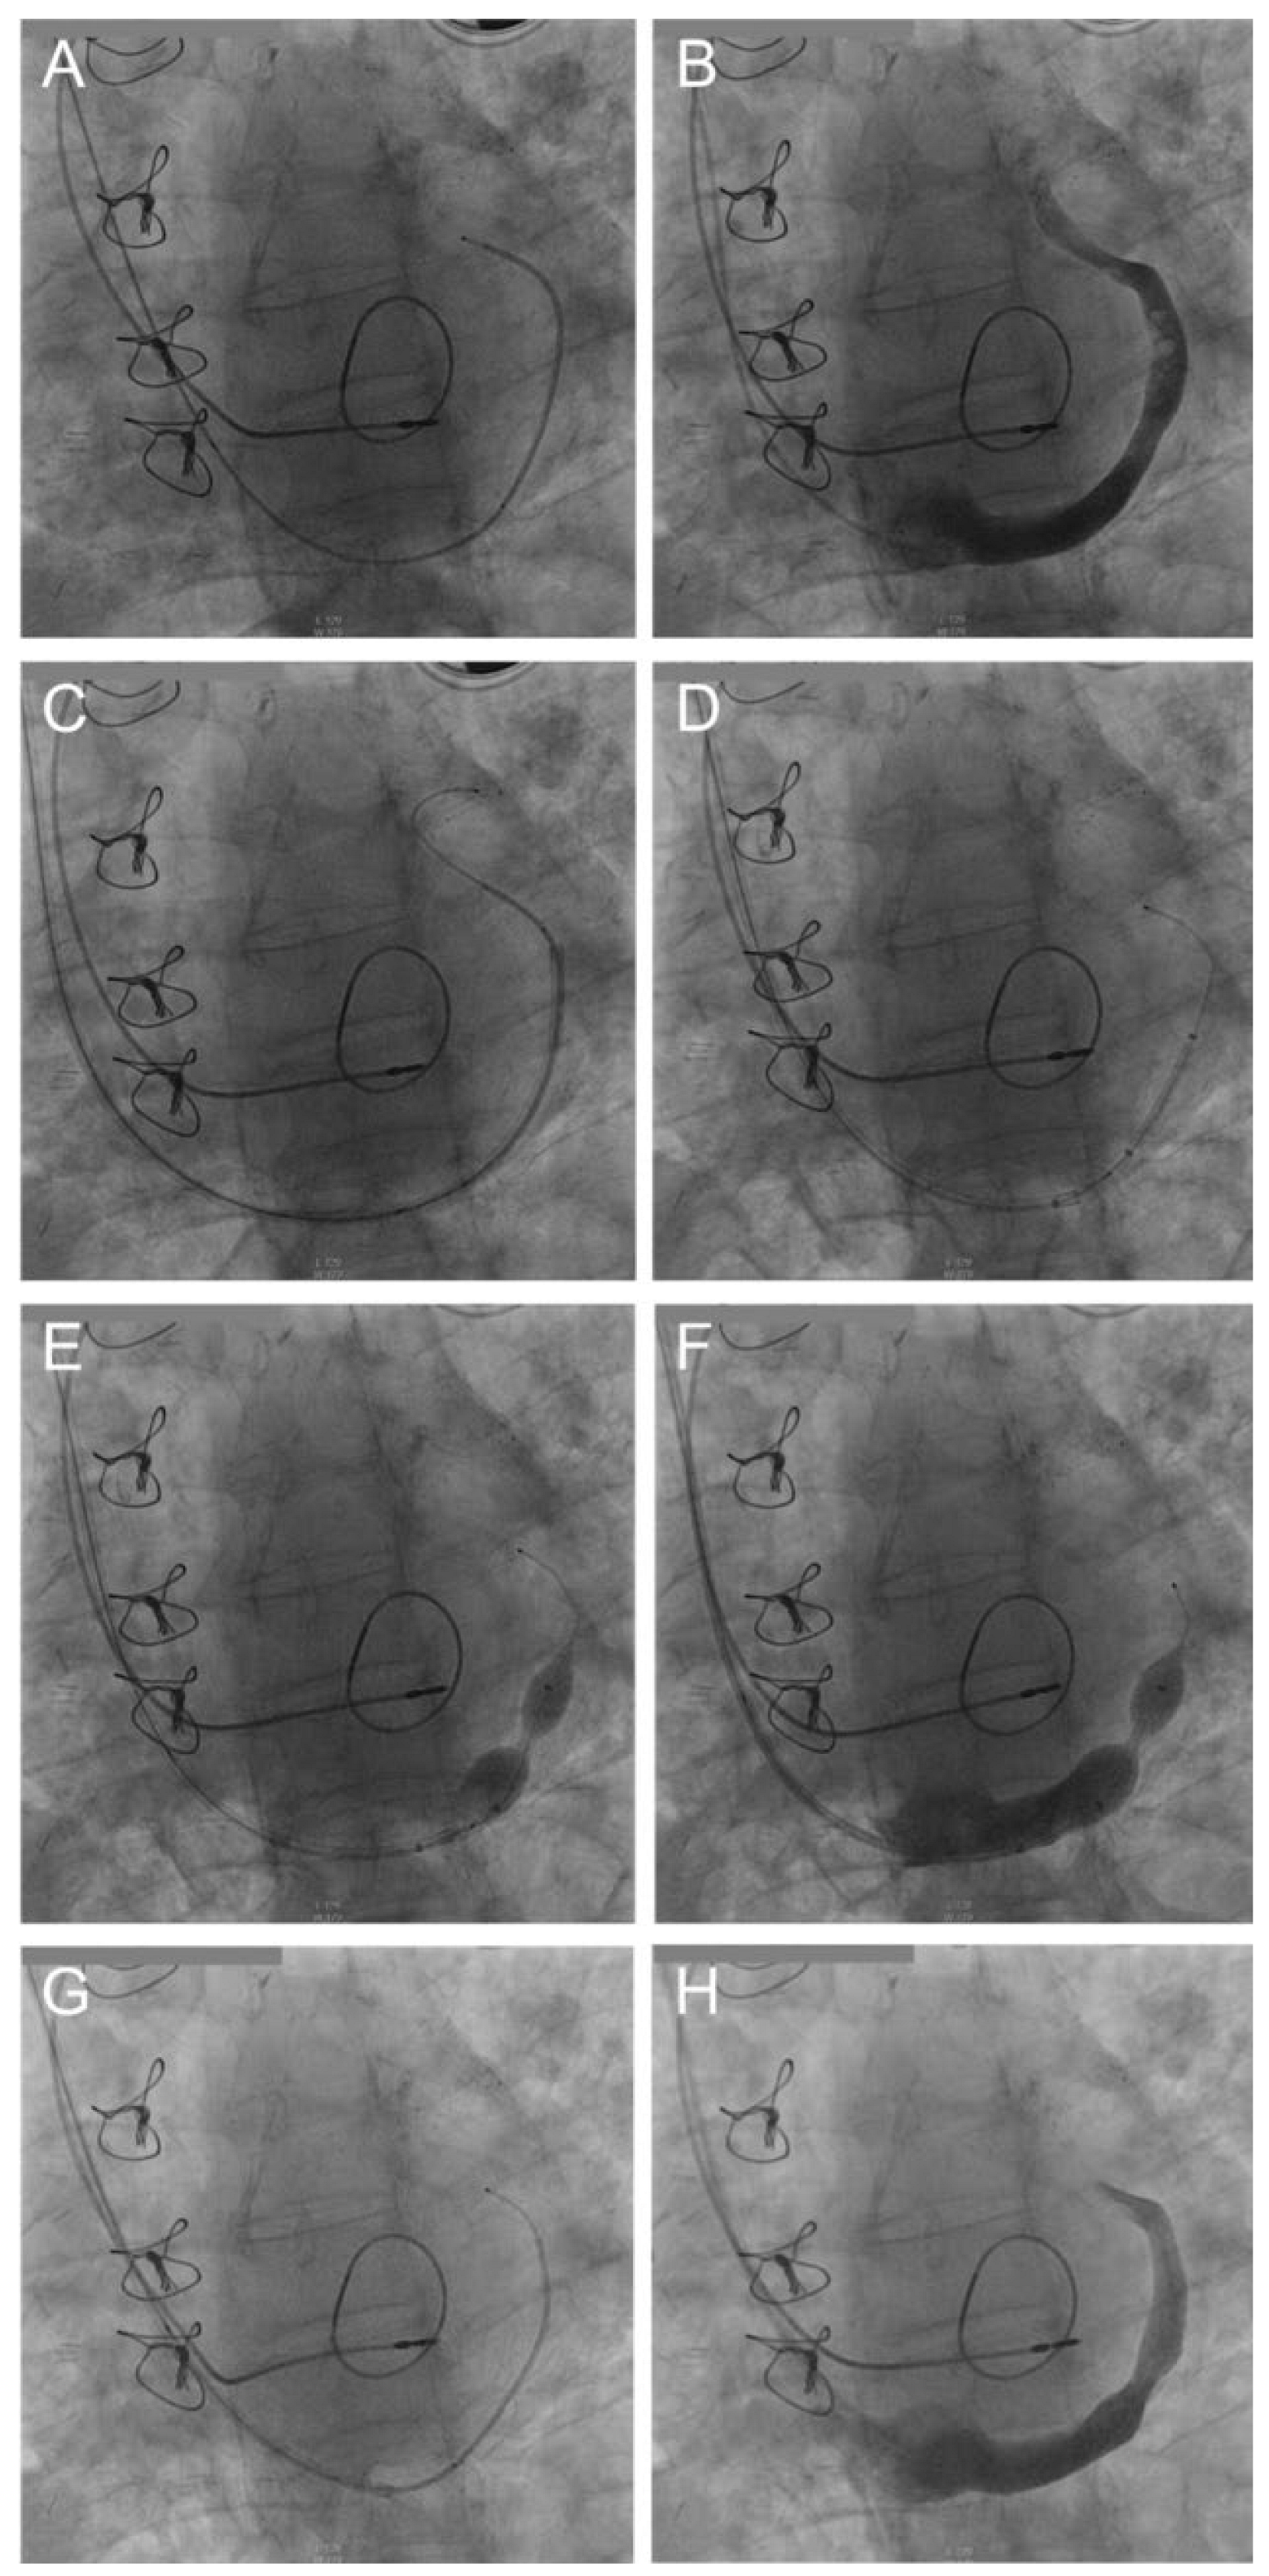

We applied the device via the right internal jugular vein. A 9F sheath was introduced into the vein, and then a 5F multipurpose catheter was carefully placed deep in the main vessel of the coronary sinus (Figure 2A). Injection of contrast allowed us to visualise the anatomy of the coronary sinus in order to define and measure the most suitable position for the implantation of the device (Figure 2B). Then a Supra Core 35 guidewire was placed deep into the coronary sinus (Figure 2C) and intravenous heparin administered. A 9F straight guiding catheter was placed with a “mother and child technique” distal to the planned implantation site; then the 5F multipurpose catheter was retracted. Next, the Reducer™ inside the guiding catheter was advanced to the anticipated site of implantation (Figure 2D). Then the 9F guiding catheter was retracted to the third or proximal mark of the stent and the balloon was inflated with 4 and 6 bar pressure, while backed up with the guiding catheter (Figure 2E). Injection of contrast via the guiding catheter demonstrated full occlusion of the coronary sinus by the balloon of the Reducer™ (Figure 2F). The pressure was maintained for 30 seconds before the balloon was deflated. The guiding catheter was then pulled back. Finally, a multipurpose catheter was passed through the Reducer™ (Figure 2G) and the coronary sinus was visualised by injecting contrast distal to the implanted device (Figure 2H).

Figure 2.

Implantation of the coronary sinus (CS) Reducer in 8 steps. (A) Positioning of a multipurpose catheter in the CS. (B) Visualisation of CS anatomy and identification of optimal implantation site. (C) Placement of a guidewire deep into the CS. (D) Positioning of guiding catheter just distally to the planned implantation site. (E) Inflation of the Reducer™. (F) Demonstration of full CS occlusion by contrast injection. (G) Passage of a multipurpose catheter through the Reducer™. (H) Check angiography.